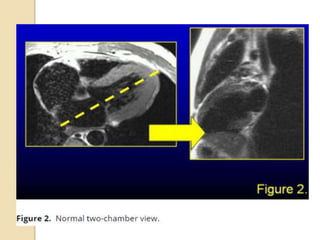

Two chamber view

 To achieve a two-chamber scout view,

a true axial view through the left

ventricle should be obtained, and then

an oblique coronal scout view should

be positioned parallel to the

interventricular septum

Two chamber view To achieve a two-chamber scout view, a true axial view through the left ventricle should be obtained, and then an oblique coronal scout view should be positioned parallel to the interventricular septum